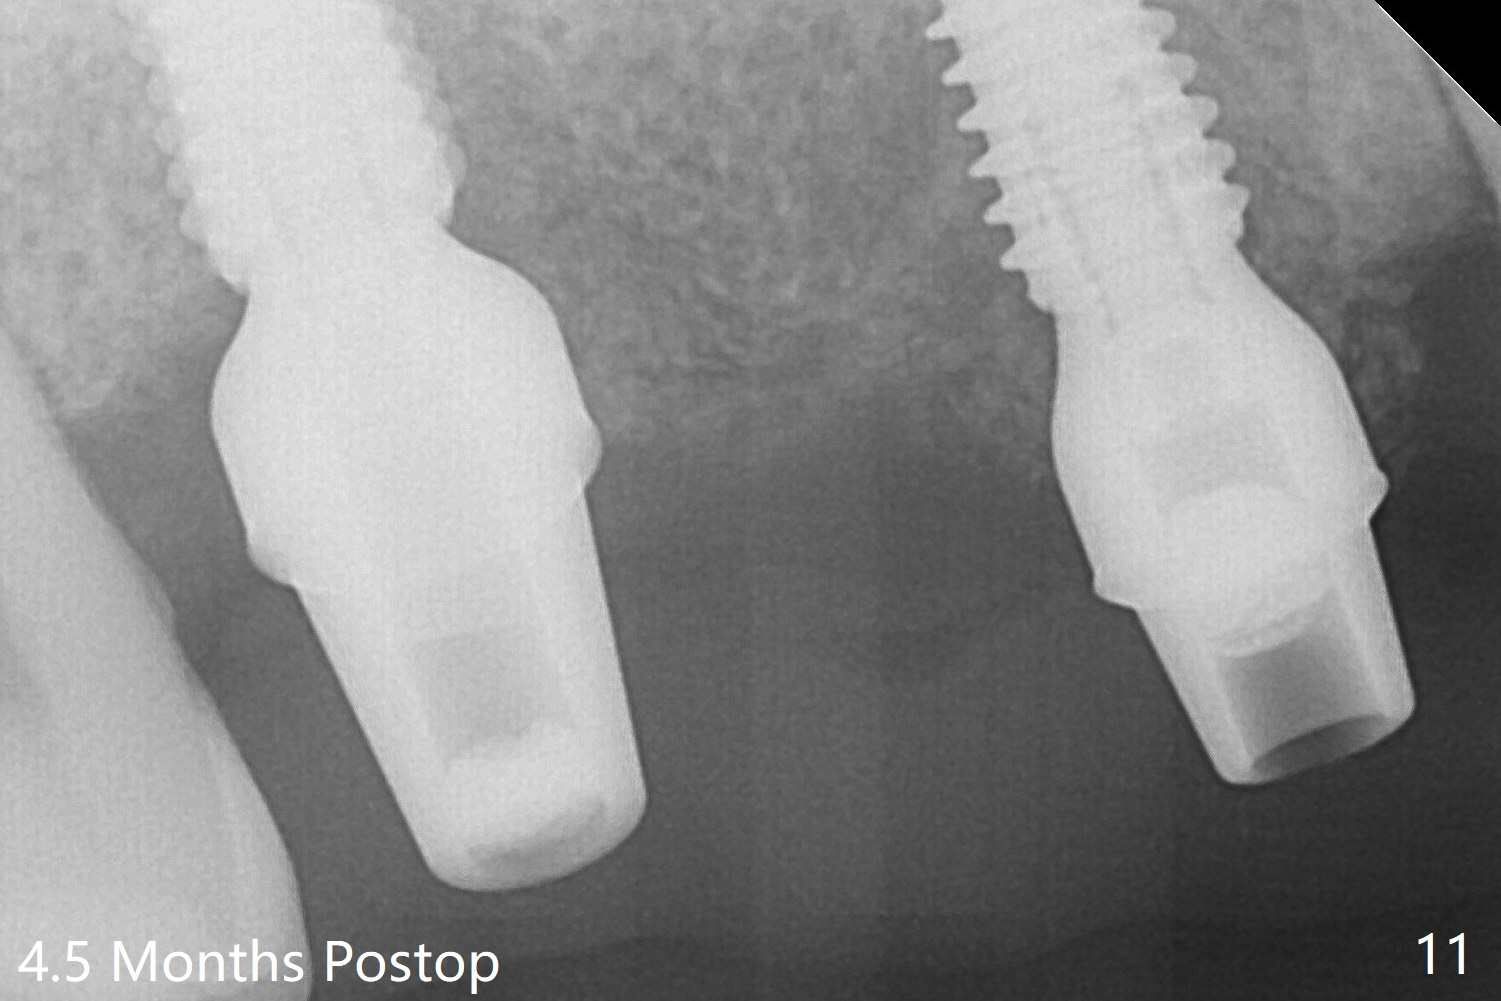

Then a 5x11.5 mm is placed at #3 subcrestal proximally after sinus lift with Vanilla graft (without sinus membrane perforation; Fig.8). The implants seem to have been osteointegrated 4.5 months postop (Fig.11). The 6.5x7(5) and 5.5x4(5) mm abutments are parallel.